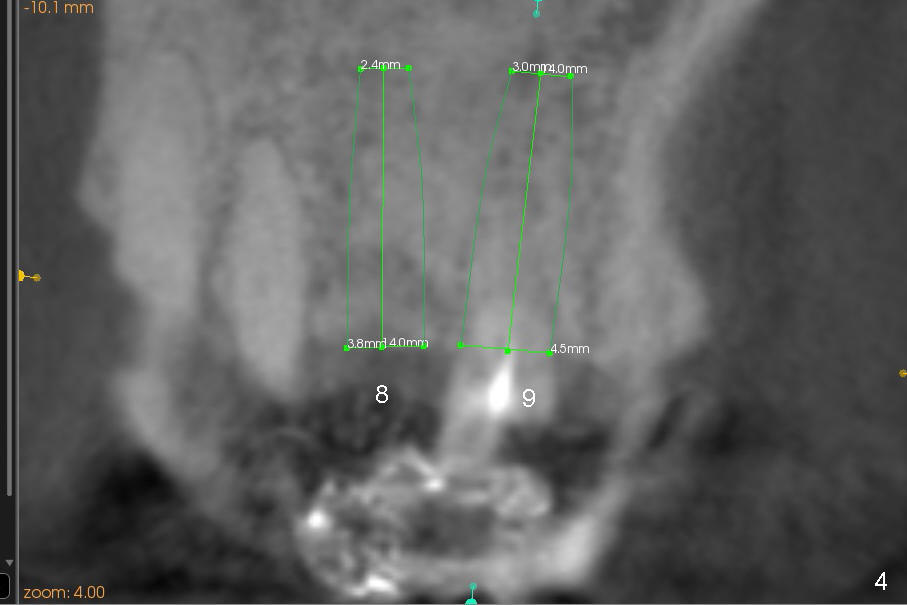

First molar occlusion is planned (1,2). The tooth #3 was extracted a year ago (Fig.1 (CT sagittal section). There is more bone loss distally so that bone graft (red circles) is required post implantation (5.3x14 mm). Buccolingual width is not severely compromised (Fig.2 (coronal section), 3).

Buccal atrophy at the site of #8 dictates a smaller implant than that of #9 (Fig.4-7).